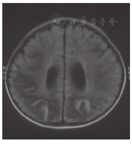

饮食治疗原则为限制果糖摄入,避免食用水果、奶类、南瓜、动物肝脏及胡萝卜,鼓励肉、蛋、豆类、鱼虾、粮食及菜类等食物,避免长时间饥饿。为缓解肌紧张,口服盐酸苯海索片及氯硝西泮。为保证营养,给予左卡尼汀、维生素B12、A、D等支持治疗。治疗后1个月后复查脑MRI显示侧脑室扩张,提示脑萎缩(图4)。随访至3岁,智力逐渐恢复,痉挛型截瘫逐渐好转,治疗后未再出现呕吐、腹痛及抽搐等症状。